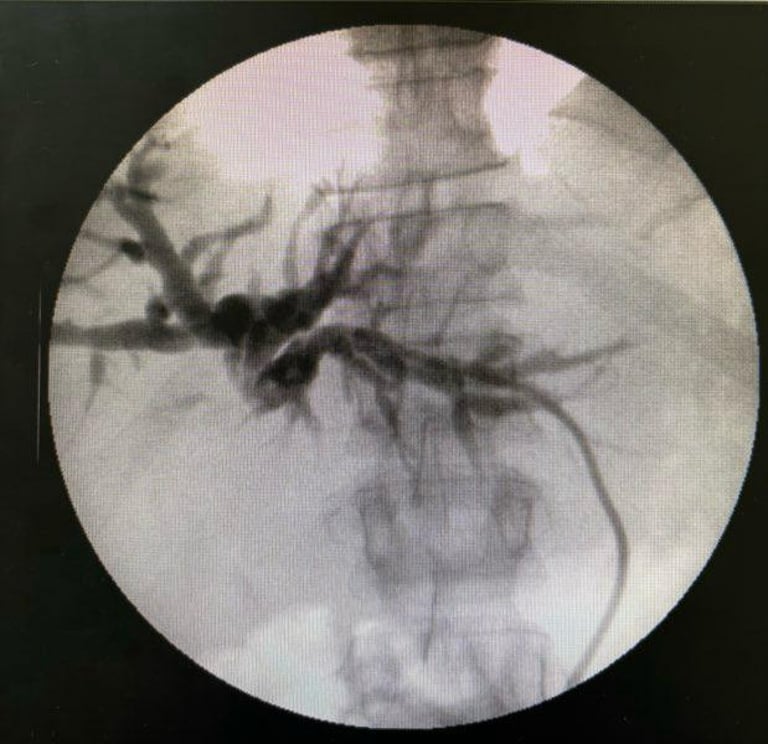

Procedimentos percutâneos

da via biliar

Quando os canais da bile ficam obstruídos (por cálculos, estreitamentos ou tumores), podemos tratá-los de forma minimamente invasiva por meio de punção através da pele, guiada por ultrassonografia, com o intuito de drenar a bile. Esse método é uma opção importante quando a via endoscópica não é possível ou não resolveu o problema, podendo ser o tratamento definitivo ou uma ponte para o tratamento cirúrgico em um segundo momento